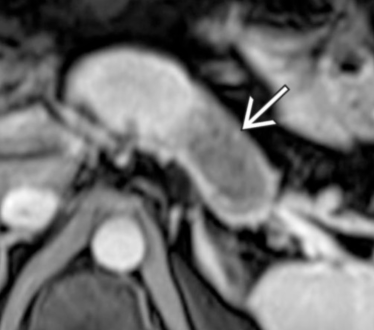

- Infiltration artérielle: <180° vs >180° et cranio-caudalement >2cm vs <2cm

- Infiltration veineuse: Contact, engainement, sténose, occlusion

- Infiltration de la lame rétroporte (entre l’AMS et l’uncus)

Lame rétroporte

Critères de résequabilité